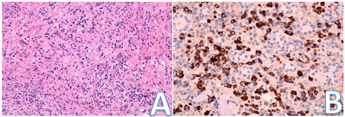

入院后完善相关检查:血液分析(五分类):嗜酸性粒细胞(#) 0.69×109/L↑;嗜酸性粒细胞(%) 13.00%↑;红细胞4.28×1012/L ↓;血红蛋白129.0 g/L ↓;红细胞压积37.6%↓;肝肾功能:尿酸477 umol/L ↑;白蛋白36.0 g/L ↓;球蛋白44.7 g/L ↑;白球比0.8 ↓。凝血功能五项、尿分析+尿沉渣定量、粪便常规+潜血+寄生虫未见异常。甲功五项、男性肿瘤标志物:未见异常,感染性疾病筛查(输血科):乙肝病毒表面抗体30.62 mIU/ml ↑;免疫球蛋白+补体定量测定:免疫球蛋白G 2040.2 mg/dl ↑,自身免疫抗体全套2(ANA核型、ANA定量、ENA谱):阴性。颌下腺MR平扫诊断内容:1.左侧腋窝淋巴结肿大;2.双侧颌下区、颈部小淋巴结显影。头颅MRI平扫诊断内容:颅脑MRI扫描未见明显异常。CT-平扫全腹诊断内容:胆囊切除术后改变。CT-平扫胸部及心脏诊断内容:右肺上叶少许炎症。免疫球蛋白G4 53.6 g/L↑,考虑IgG4相关性疾病,至华中科技大学同济医学院附属同济医院就诊,磁共振-眼眶平扫:双侧泪腺肿胀;冠状位TW1扫描所及双侧腮腺体积增大;双侧筛窦和额窦炎。再次重新阅读我院头颅MRI(图1)及颌下腺MRI (图2A、B)可发现患者泪腺、腮腺及颌下腺均肿大。于华中科技大学同济医学院附属同济医院口腔科行左侧颌下腺切除,病检结果:灰红不整涎腺组织4.6 cm×3 cm×2 cm,临床已部分切开,切面灰红分页状,未见明确实性肿块,病理诊断:(左颌下肿物)镜下见涎腺小叶被增生的纤维结缔组织分隔,小叶内外可见浆细胞为主的慢性炎性细胞浸润,淋巴滤泡增生,免疫组化结果提示IgG阳性细胞数热点区约100个/HPF,且IgG4/IgG大于40%,考虑IgG4相关性疾病可能性大。免疫组化:浆细胞IgG4热点区约150个/HPF,且IgG4/IgG大于40%,CD19(+),κ和λ(部分阳性,无限制性轻链表达),淋巴滤泡CD20(+,阳性对照+),CD21(FDC网+),ki-67(生发中心高,滤泡间区散在+);滤泡间区CD3(散在+)(图3A、B)。

患者双侧颌下腺肿大、眼睑水肿、头痛,入院前已于眼科专家门诊就诊,入院后请口腔科、神经内科会诊。口腔科会诊意见:查体:双侧颌下腺肿大,压痛(一),质地中等偏硬,边界清楚,可活动,周围未扪及肿大淋巴结。考虑诊断:双侧颌下淋巴结炎?双侧颌下腺肿物?神经内科会诊意见:考虑颌下腺炎症,淋巴结炎(淋巴结病变),耳大神经痛。建议查CRP、PCT,口腔科会诊,必要时抗感染治疗。阻滞神经痛:普瑞巴林,并逐渐加量。疼痛好转后逐渐减量。营养神经:维生素B1,弥可保。口腔科及神经内科会诊均考虑颌下腺炎症,患者颌下腺无痛性肿大,颌下腺无压痛,口服抗生素症状未改善,且无法解释眼睑水肿及头痛等症状,遂考虑颌下腺感染性炎症可能性不大。患者双侧颌下腺对称性肿大,颌下腺MRI未提示占位性病变,考虑颌下腺肿瘤可能性不大。后经武汉某医院口腔科教授会诊,考虑IgG4-RD,查免疫球蛋白G4 53.6 g/L↑,至华中科技大学同济医学院附属同济医院就诊,行左侧颌下腺切除,病检结果:灰红不整涎腺组织4.6 cm×3 cm×2 cm,临床已部分切开,切面灰红分页状,未见明确实性肿块,病理诊断:(左颌下肿物)镜下见涎腺小叶被增生的纤维结缔组织分隔,小叶内外可见浆细胞为主的慢性炎性细胞浸润,淋巴滤泡增生,免疫组化结果提示IgG阳性细胞数热点区约100个/HPF,且IgG4/IgG大于40%,考虑IgG4相关性疾病可能性大。考虑IgG4-RD诊断明确。IgG4-RD同时累及到泪腺、唾液腺时,亦可诊断为米库利奇病(Mikulicz,s,disease,MD)。

IgG4-RD是一种慢性自身免疫炎症介导的疾病,可累及全身多个器官和组织,其中胰腺最常见,其次是唾液腺[4,5,6]。因受累脏器不同,患者的临床表现差异较大[2,3],导致患者就诊于不同专科。本病最常见的临床表现为显著升高的血清IgG4水平和肿块样病灶,特征性的病理改变是诊断IgG4RD的重要依据,病理检查对鉴别诊断排除模拟疾病亦至关重要,因此建议有条件者应行组织活检[7]。2011年日本制定的IgG4-RD综合诊断标准[8],是临床医师应用最广泛的标准:(1)单个或多个器官弥漫性或局限性肿胀、团块;(2)血清IgG4>1.35 g/L;(3)受累组织明显的淋巴细胞、浆细胞浸润及纤维化,IgG4+浆细胞>10个/高倍视野,IgG4+/IgG+浆细胞比例>40%。符合上述3项可确定诊断,符合第1和第3项为疑诊,符合第1和第2项为可能诊断。本例男性患者,颌下腺、腮腺及泪腺肿胀,IgG4>1.35 g/L,浆细胞IgG4热点区约150个/HPF,且IgG4/IgG大于40%,IgG4-RD诊断明确。